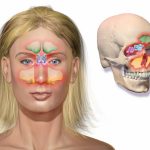

Гайморит у взрослых проявляется появлением нарастающей боли в районе носа. По утрам болезненные ощущения беспокоят меньше, но к вечеру нарастают. Голос становится гнусавый, носовое дыхание затруднено. Симптомы гайморита (фото 1) сопровождаются появлением выделений из носа, нарушением сна, повышенной утомляемостью, приступами кашля, появлением озноба.

Выглядит гайморит (см. фото 2) у взрослых и детей не очень приятно. Признаки гайморита у взрослых выражены потерей обоняния, появлением слезотечения, повышенным потоотделением. Так же появляется отечность на лице, неприятные запахи из носа, рта. Может присутствовать после приема пищи очень неприятное послевкусие – это тоже признаки гайморита у взрослых.